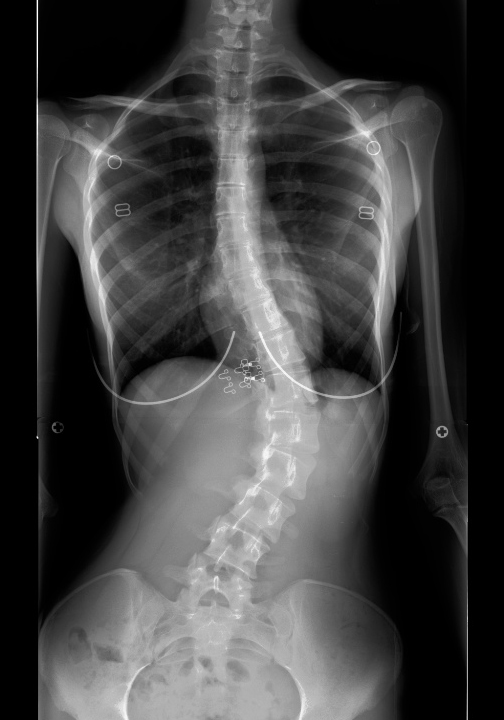

| Pre-op | Post-op |